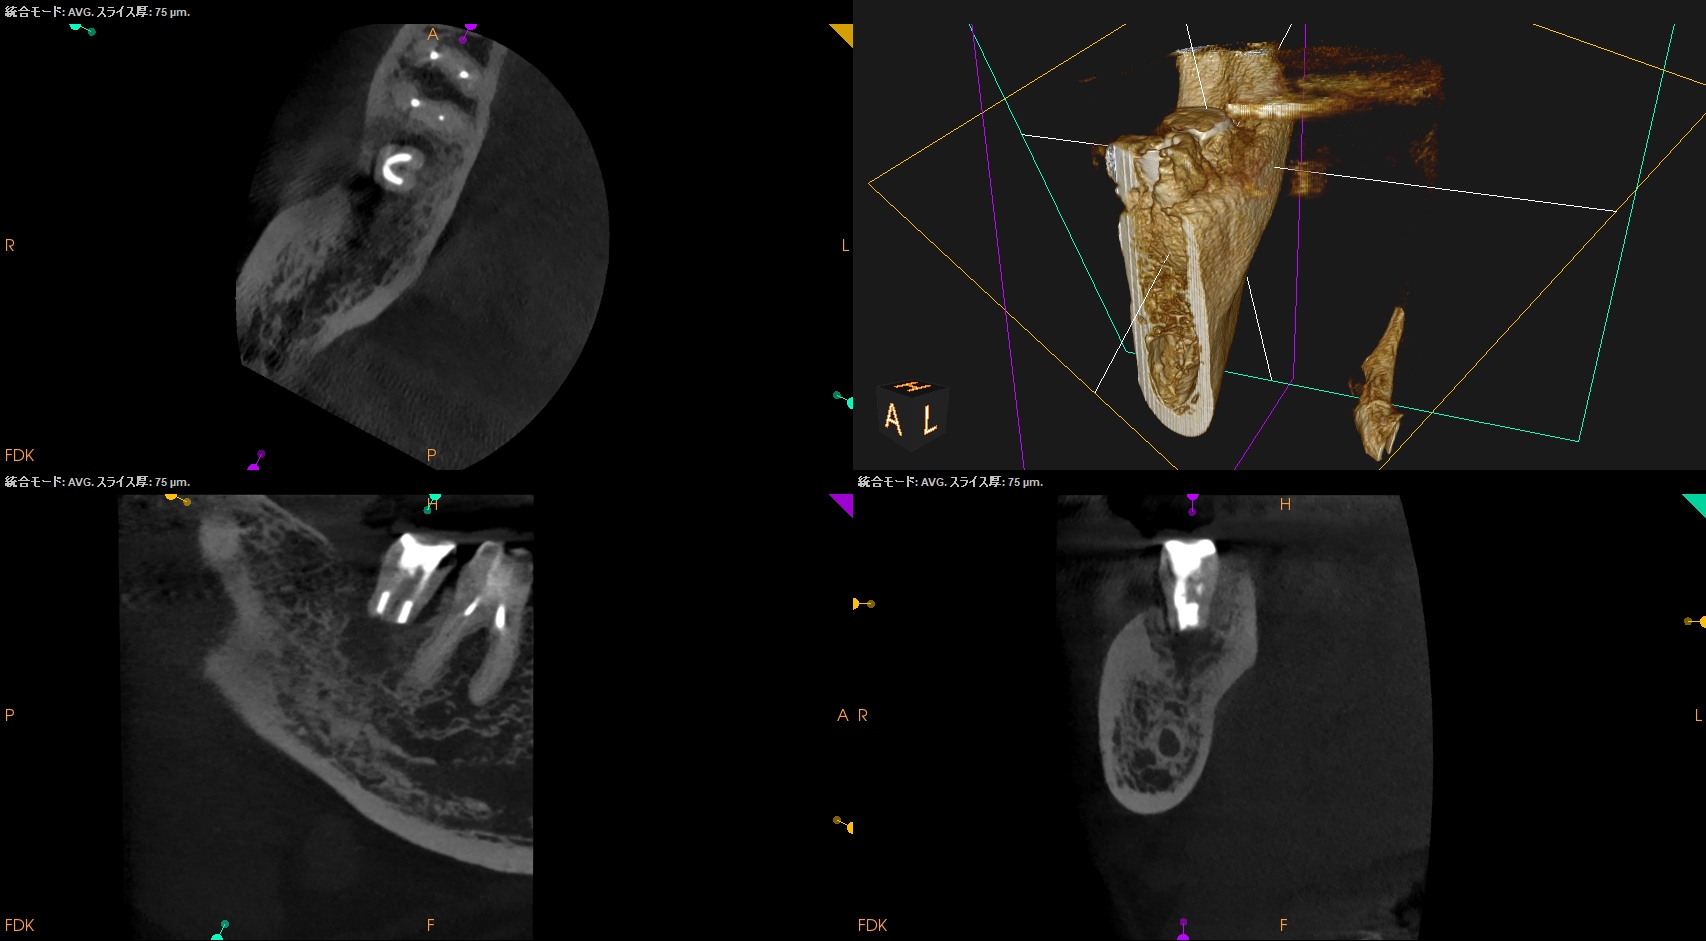

CBCT(2025.5.19)

ML

MB

D

確かに…

折れていると言われかねない状況だ。